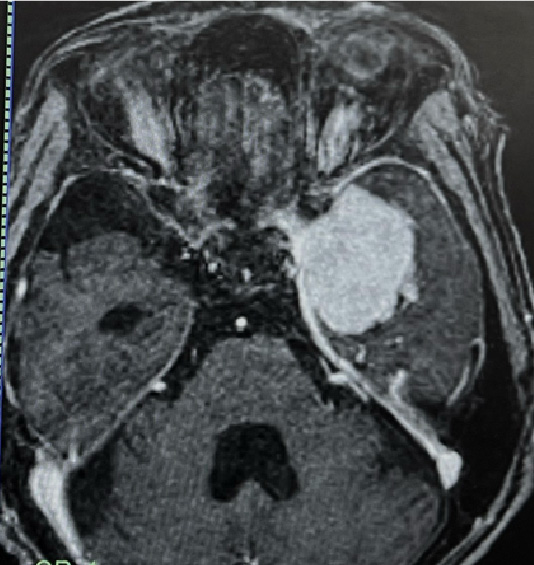

嗅神経芽細胞腫:鼻腔上部に発生する悪性腫瘍

術前MRI

術後MRI